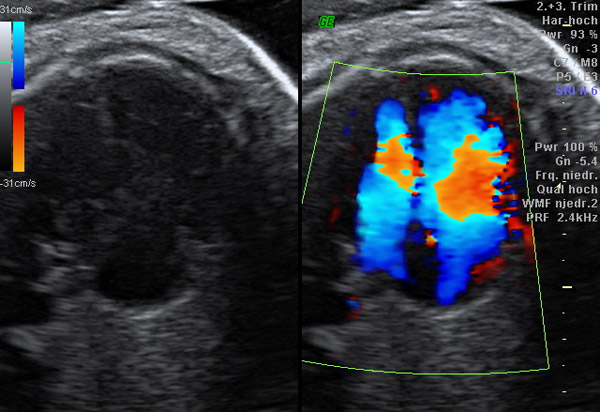

Spezielles Ultraschallverfahren zur Messung von Blutströmen in kindlichen

und mütterlichen Gefäßen. Dadurch kann die Befindlichkeit des Föten,

die Versorgungsqualität des Mutterkuchens und die Neigung zur Gestose

(früher als Schwangerschaftsvergiftung bezeichnet) untersucht und

vorhersehend überprüft werden. Diese Untersuchung ist fester Bestandteil

der sonographischen Feindiagnostik und sollte auch bei Risikoschwangerschaften

ggf. regelmäßig durchgeführt werden. Typische Indikationen sind:

mütterl. Bluthochdruck

Schwangerschaftsdiabetes

wachstumsreduzierte Kinder

Fruchtwasser-Auffälligkeiten

Mehrlingsschwangerschaften

entsprechende Vorgeschichte

u.v.m.